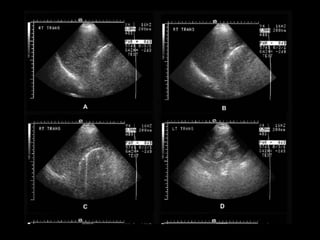

A bedside sonogram was performed and the gallbladder could

not be confidently identified. The patient was sent to the radiology

department for another abdominal ultrasound study. Selected

ultrasound images, including the right upper quadrant,

are shown in Figure 1.

IMAGING DIAGNOSIS OF ACUTE

CHOLECYSTITIS

• Abdominal rx: 15% stones calcified

• Ultrasound : > sensitive

• Symptomatic:

– 80% without

DIAGNOSIS OF ACUTE CHOLECYSTITIS

• CLINICAL PRESENTATION

• SIGNS OF GALLBLADDER INFLAMATION ON

SONOGRAPHY OR CT

– GALLBLADDER WALL THICKENING (>3 TO 5MM)

– PERICHOLECYSTIC FLUID

– SONOGRPHIC MURPHY’S SIGN

• 6.

Abdominal examination revealeddiminished bowel sounds, moderate tenderness in the right upper quadrant, and a Murphy’s sign. There was no tenderness on rectal examination and stool was guiac negative. An intravenous line was started and blood specimens were obtained. Intravenous fluids, insulin, and ampicillin/sulbactam were administered Blood test results (units for electrolytes, mEq/L and chemistry values, mg/dL, except where noted): WBC 19,700/mm3, hematocrit 49%, platelets 246,000/mm3. Na 132, K 4.1, Cl 101, CO2 22, BUN 24, creatinine 1.4, glucose 406. ALT 100 U/L (normal: 7–37), AST 65 U/L, alkaline phosphatase 61 U/L (normal: 39–117), total bilirubin 1.6 (normal: 0.2–1.2), lipase 110 U/L (normal). A bedside sonogram was performed and the gallbladder could not be confidently identified. The patient was sent to the radiology department for another abdominal ultrasound study. Selected ultrasound images, including the right upper quadrant, are shown in Figure 1.